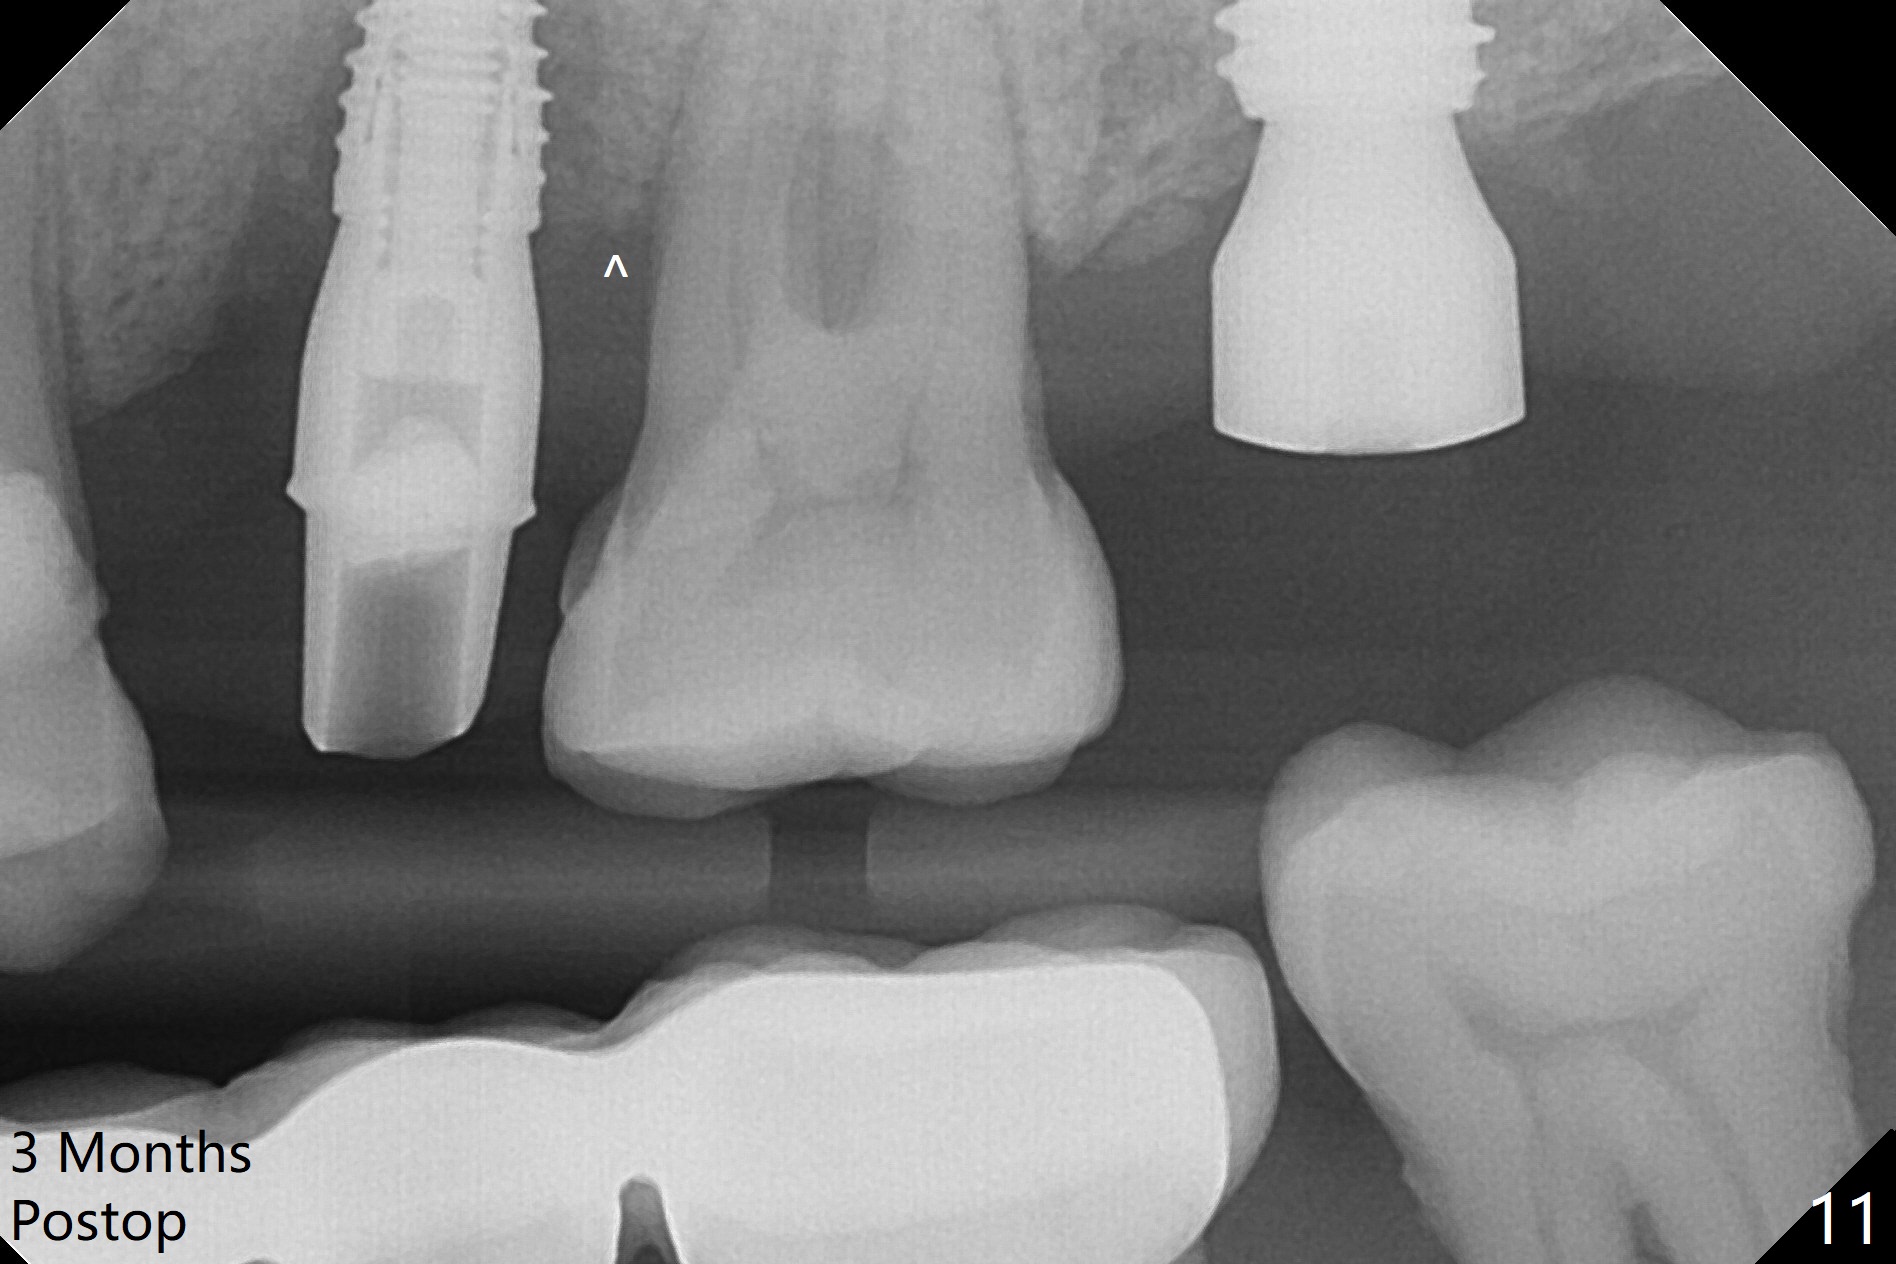

Initial osteotomy depth is 18 mm (Fig.1 green line) with 9 mm in the native bone (red line). The bone density feels to be low. There is at least 2 more mm bone apically (pink line). The depth is increased by 2 mm so that when a 3.8x15 mm implant is placed, there is 10-11 mm implant/bone contact (Fig.2 red line). There is large bony defect (Fig.3 *), which is bone grafted (Fig.4 *). Finally a longer abutment is placed (4.5x5.5(5) in Fig.4 vs. 4.5x4(5) in Fig.2,3). The 5 mm cuff does not look too long buccally (Fig.5) or palatally (Fig.6). To prevent postop buccal gingival overgrowth (2), the buccal margin of an immediate provisional is subgingival (Fig.7-9 *). Bone density between #13 and 14 appears to increase 3 months postop (Fig.10). The implant seems to be equi-crestal (Fig.11 ^). There seems to be more bone growth (i.e., decreasing gap) 6 months postop (Fig.12). Impression is taken. A crown is delivered nearly 7 months postop (08/07/2017). While there is minimal bone loss at #13 and 15 three years and 4 months post cementation, the tooth #14 and 18 are mobile (Fig.13,14).